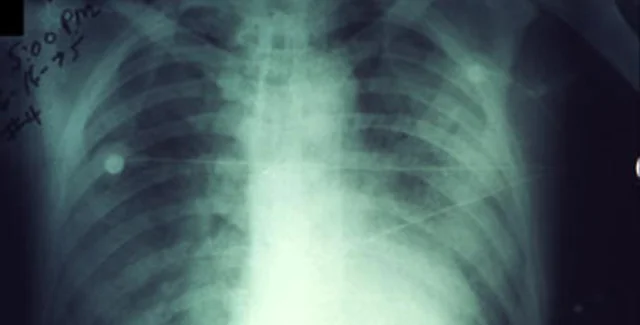

Легочная чума – одна из трех основных форм проявления чумы. Вызывается бактериями Yersinia pestis и поражает органы дыхания. Более опасна, чем бубонная чума, но встречается реже. При отсутствии лечения смертность чрезвычайно высокая, вплоть до 100%.